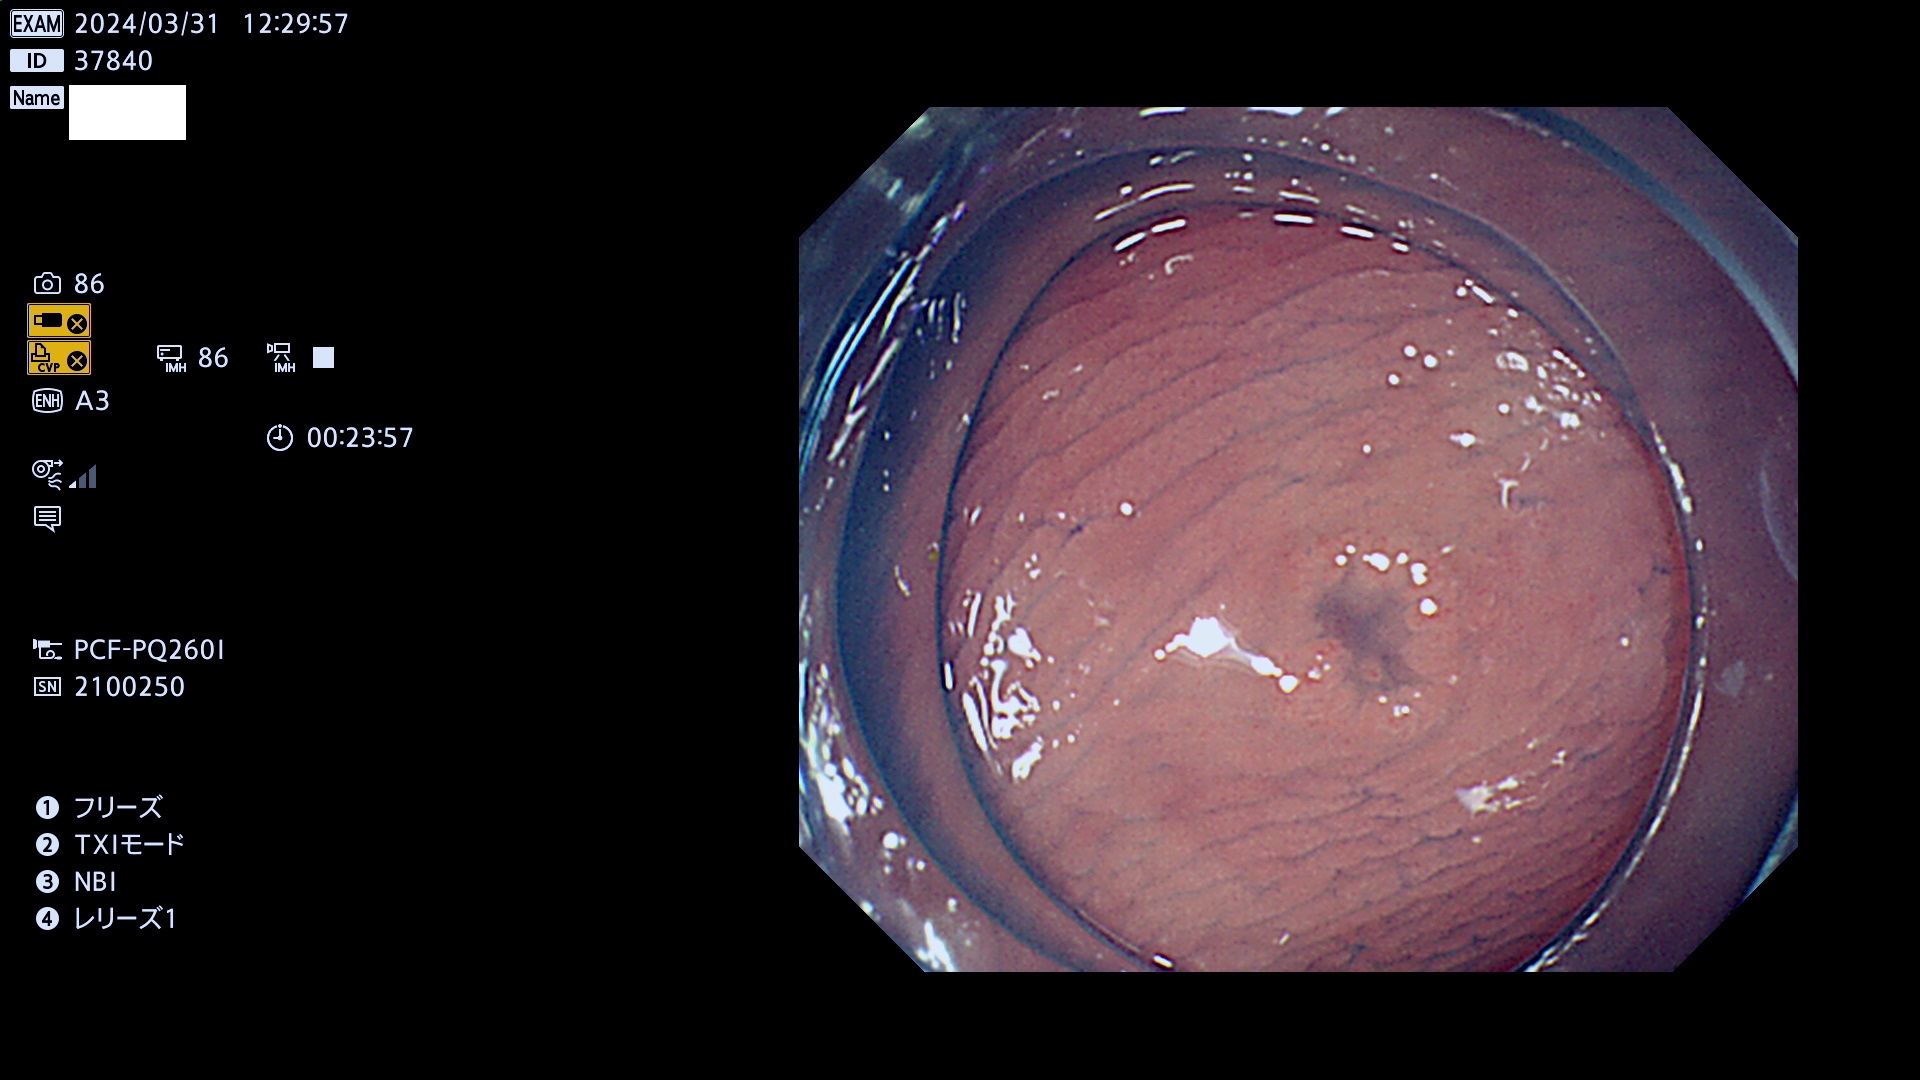

表面型腺腫(Flat Adenoma)の中で、完全に平坦な物をUb、陥凹している物をUcと呼びます。平坦隆起型(Ua)よりも、発見が難しく危険な病変です。

毎週の検査(木・金・土・日)に発見されたUb、Uc型・腺腫を、その週の日曜の夜にUPし1週間、提示します。

抽出の対象期間 2024年3月28日(木)〜3月31(日)の4日間(40件の検査)3件 (3/40=8%)